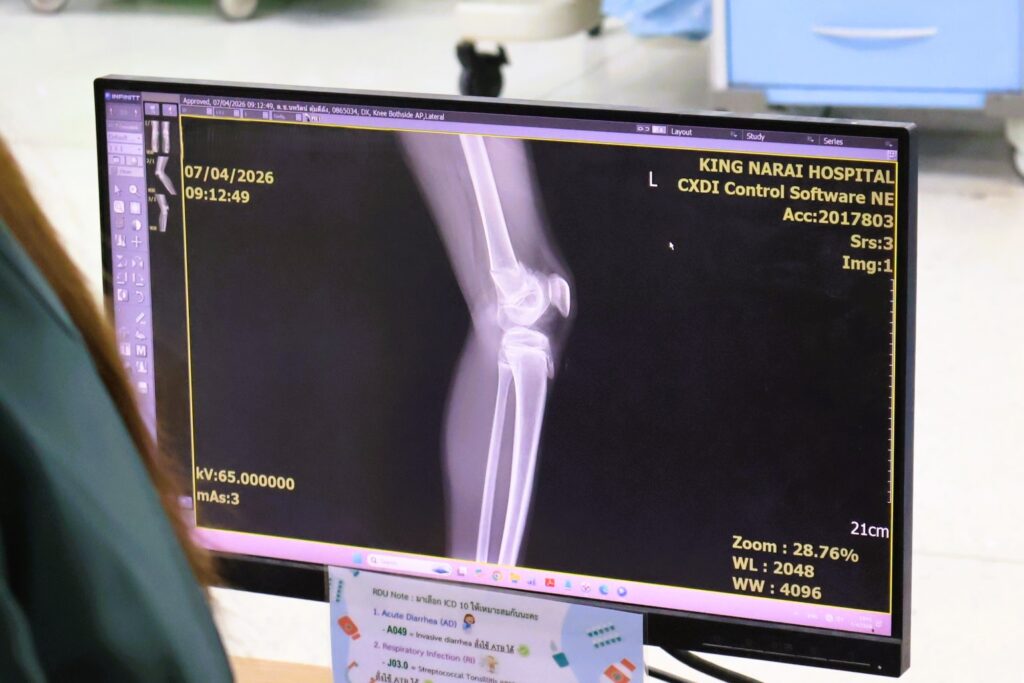

วันที่ 7 เมษายน 2569 เวลา 10.30 น. ณ โรงพยาบาลพระนารายณ์มหาราช นายวีรพงศ์ ฤทธิ์รอด ผู้ว่าราชการจังหวัดลพบุรี พร้อมด้วยหน่วยงานทุกภาคส่วน ได้เดินทางเข้าเยี่ยมอาการของเด็กนักเรียนที่ได้รับบาดเจ็บจากอุบัติเหตุรถรับส่งนักเรียนชนกับรถบรรทุกพ่วงบริเวณ ถนน ใกล้โรงฆ่าสัตว์โคกตูม ซอย 0 ถนนหมายเลข 3333 ตำบลโคกตูม อำเภอเมืองลพบุรี จังหวัดลพบุรี เมื่อช่วงเช้าที่ผ่านมา ในการนี้ ผู้ว่าราชการจังหวัดได้พูดคุยให้กำลังใจแก่เด็กนักเรียนและผู้ปกครอง เพื่อเป็นการสร้างขวัญและกำลังใจ โดยผู้ว่าฯลพบุรี ได้กำชับให้บูรณาการหน่วยงานที่เกี่ยวข้องดูแลเรื่องสวัสดิการและสิทธิประโยชน์ ประกันภัย ทั้งหมด นอกจากนี้คณะแพทย์พยาบาลได้ทำการดูแลรักษาอาการบาดเจ็บของเด็ก ๆ อย่างใกล้ชิด

นายวีรพงศ์ ฤทธิ์รอด ผู้ว่าราชการจังหวัดลพบุรี เปิดเผยว่าการเกิดอุบัติเหตุในครั้งนี้ เป็นรถโรงเรียนเกตุพิชัยวิทยา อำเภพระพุทธบาท จังหวัดสะบรี โดยรถตู้ดังกล่าวกำลังเดินทางไปเรียนนักเรียนเรียน ซัมเมอร์ที่โรงเรียน โดยรถบรรทุก 10 ล้อได้ขับรถมุ่งหน้าจากวงเวียนโคกตูมจะไปทางสี่แยกหนองเสาพอมาถึงที่เกิดเหตุได้กลับเลี้ยวรถกลางถนนทำให้รถตู้ที่รับส่งนักเรียนวิ่งตามมาเบรคหลบไม่ทันพุ่งเข้าชนอย่างแรงเป็นเหตุให้นักเรียนที่อยู่ในรถตู้ได้รับบาดเจ็บเบื้องต้นมีผู้บาดเจ็บทั้งสิ้น 18 คน เป็นคนขับรถตู้ 1 คน คุณครู 1 คน และเด็กนักเรียนทั้งหมด 16 คน ซึ่งผู้บาดเจ็บทั้งหมดส่งไปยังโรงพยาบาลพระนารายณ์มหาราช 10 คน โรงพยาบาลอานันทมหิดล จำนวน 7 คน และโรงพยาบาลเมืองนารายณ์ 1 คน โดยขณะนี้ อาการของนักเรียนส่วนใหญ่พ้นขีดอันตรายแล้ว มีเพียงบางส่วนที่แพทย์ยังคงต้องเฝ้าสังเกตอาการอย่างใกล้ชิด ซึ่งทางจังหวัดลพบุรีจะติดตามสถานการณ์และให้ความช่วยเหลือจนกว่าทุกคนจะกลับมาแข็งแรงและไปเรียนได้ตามปกติ